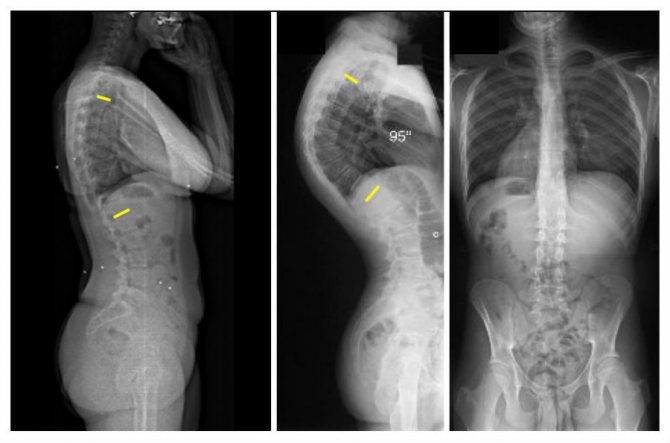

Под кифозом понимают патологическое изменение формы позвоночного столба в передне-заднем направлении. Если угол изгиба не превышает 30°, то речь идет о физиологической выпуклости. Если этот показатель выше, то врачи ставят диагноз «кифоз».

- Рентгеновское исследование. Диагностика заболевания с помощью рентгена проходит по методу Кобба. Она заключается в том, что на снимках в передне-задней проекции проводят линии по верхней границе самого верхнего нейтрального позвонка и по нижней границе самого нижнего. Перпендикулярно им проводят другие линии. На их пересечении измеряют градус угла искривления. Для категории Б и В должен быть угол искривления более 50 градусов.

Обратите внимание на то, как выглядит кифоз на рентгене

- Рентген в прямой и боковой проекции. Оценить степени искривления поможет метод Кобба. Для этого на рентгеновском снимке (боковая проекция) ставят точки в центре позвоночника на вершине изгиба и позвонках по краям. Потом их соединяют линиями в треугольник и продлевают боковые стороны. Полученный угол – это показатель степени искривления.